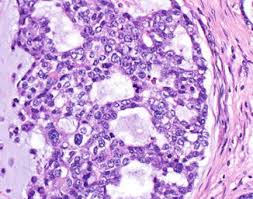

Tongue Cancer Medical Concept Or Squamous Cell Carcinoma As Malignant Tumor Disease In The Mouth Stock Photo Alamy

Tongue Cancer Medical Concept Or Squamous Cell Carcinoma As Malignant Tumor Disease In The Mouth Stock Photo Alamy from c8.alamy.com